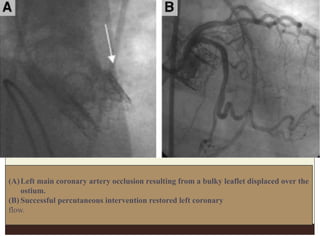

(A)Left main coronary artery occlusion resulting from a bulky leaflet displaced over the

ostium.

(B) Successful percutaneous intervention restored left coronary

flow.